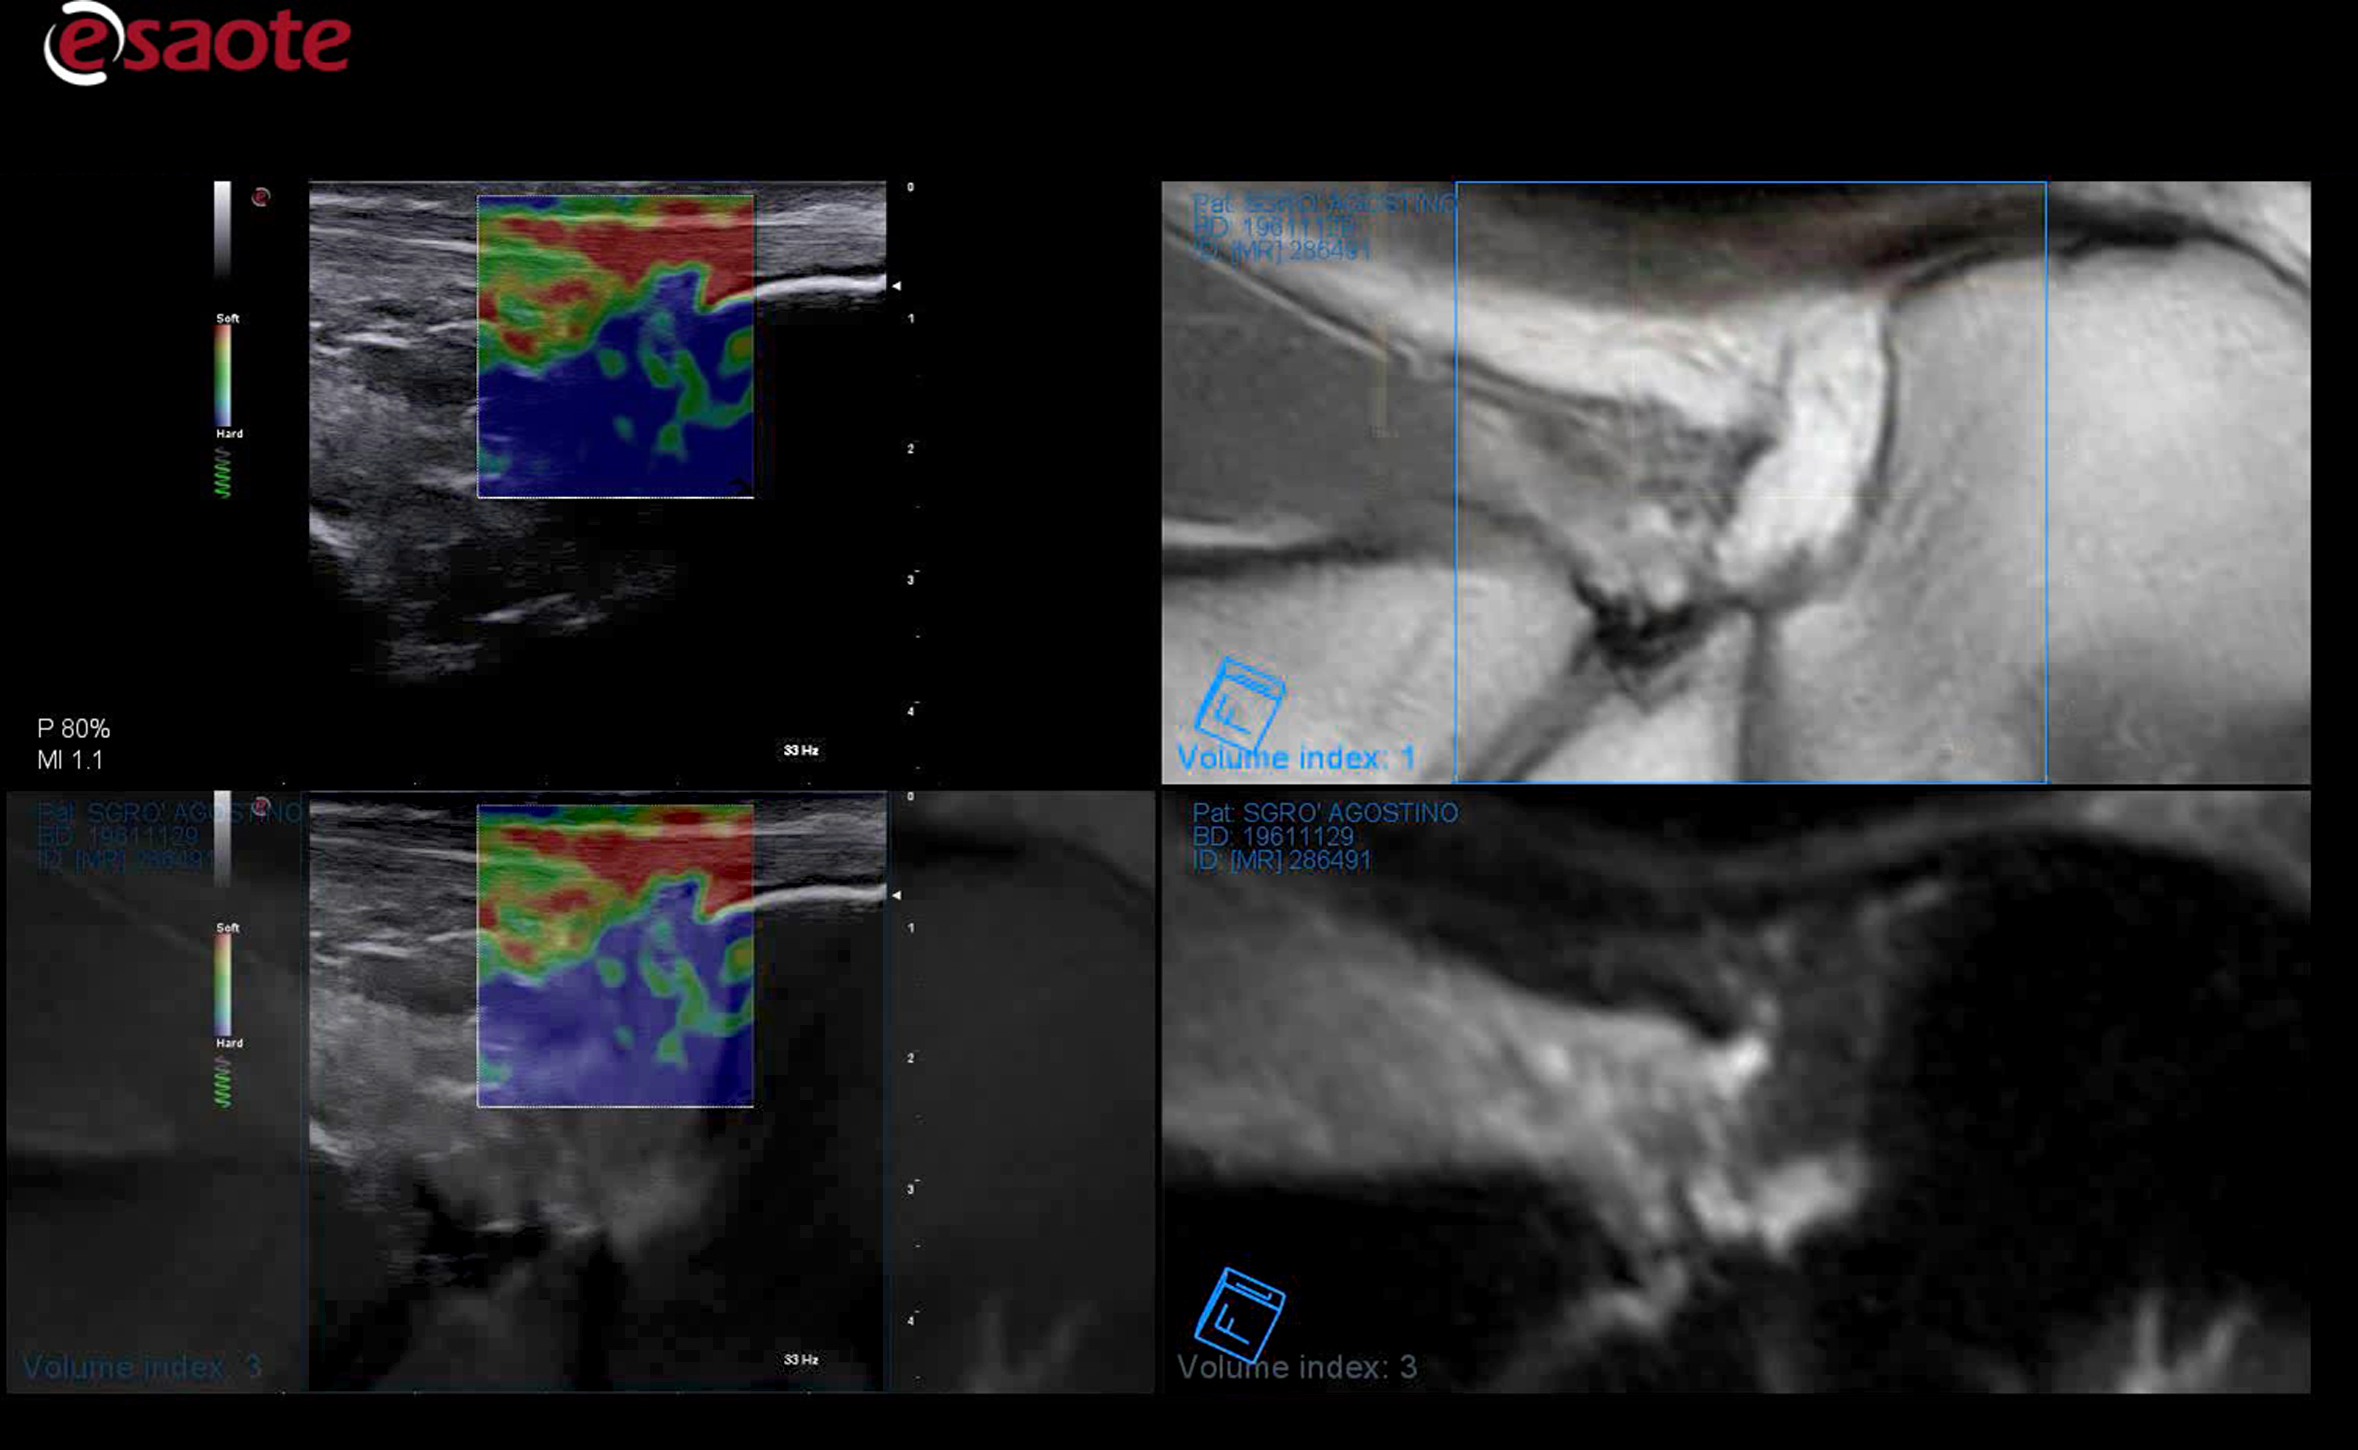

MSK/Rauma

MyLab X9o i spesialtilpasset versjon for MSK og revmatologi. Software er satt opp med spesialiserte presets for formålet. Ny 25 Mhz lineærprobe gir uovertruffen bilde-og dopplerkvalitet i overflaten.

MicroV, den nyeste dopplerteknologien fra Esaote med en enestående følsomhet selv i små kar og deteksjon av lave hastigheter. MicroV har en algoritme som helt overlegent separerer bevegelse av væske fra andre bevegelser som skaper forstyrrelser. Dette gir en helt unik dopplerfølsomhet ikke sett tidligere. Med MicroV er det mulig å endre visualiserings algoritmen for å ytterligere forsterke det du ønsker å se.

ElaXto

ElaXto (strain) lisens gir deg mulighet til å evaluere stivheten i et valgt område i real-time. Esaote har vært en pioner og stått fremst innenfor dette feltet i mange år. Dette benyttes innenfor mange områder som MSK, Bryster og Tyridea, Lever, Urologi(prostata) og gynekologi. -